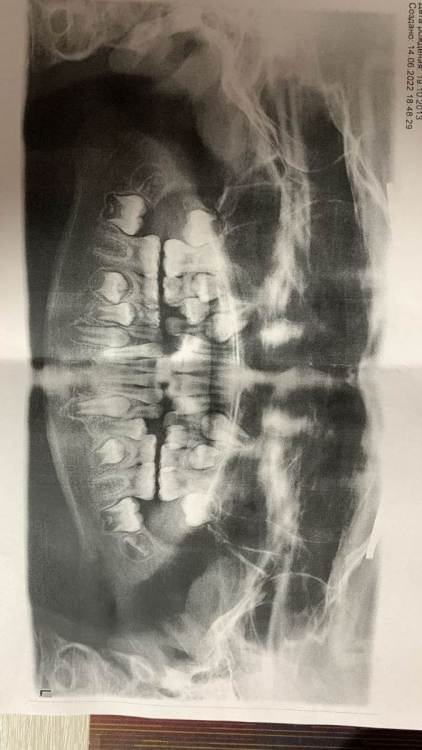

Подскажите по снимку ребенка  девочка 8 лет, говорят  что надо якобы  расширять верхнюю челюсь типо прикус не правильный  так ли это и нужно ли это делать судя по снимку? заранее спасибо.

photo_2022-06-14_22-21-05.jpg